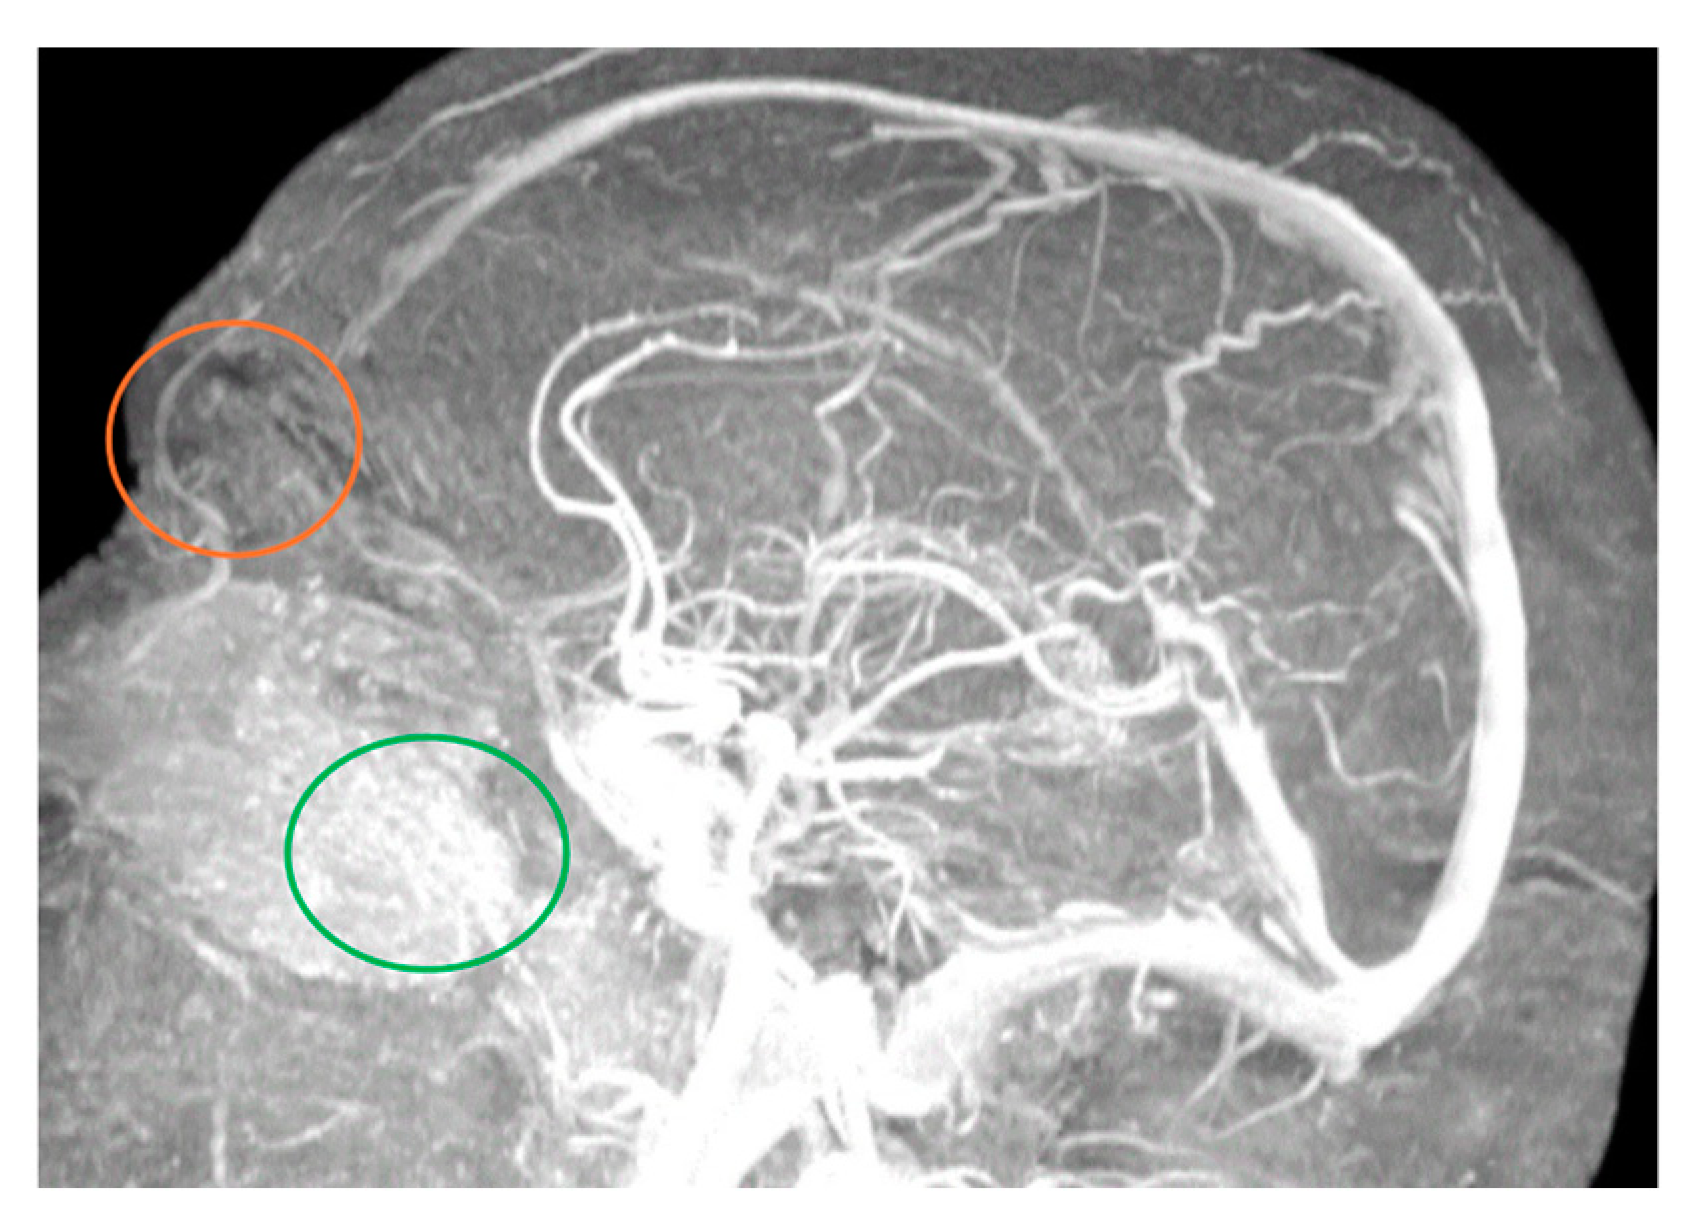

MRA easily illuminated the main blood sources of the nasal region, even if the examination protocol was not dedicated to the exploration of this region. We could identify the branches of the type 1 facial and ophthalmic arteries of the nasal region (Figure 1 and Figure 2) and at least one branch coming from the supraorbital artery (Figure 2).

Figure 2. Branches from supraorbital and ophthalmic arteries (orange circle), as well as facial artery terminal nasal branches (green circle). DT 51 yo patient. 12 min and 24 s time of exposure.